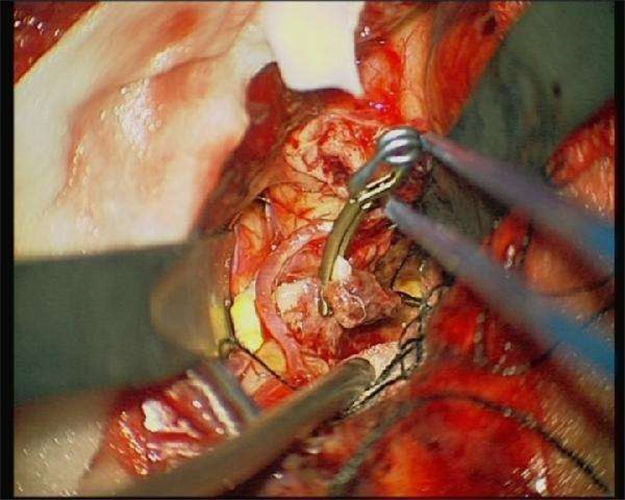

手術治療腦血栓